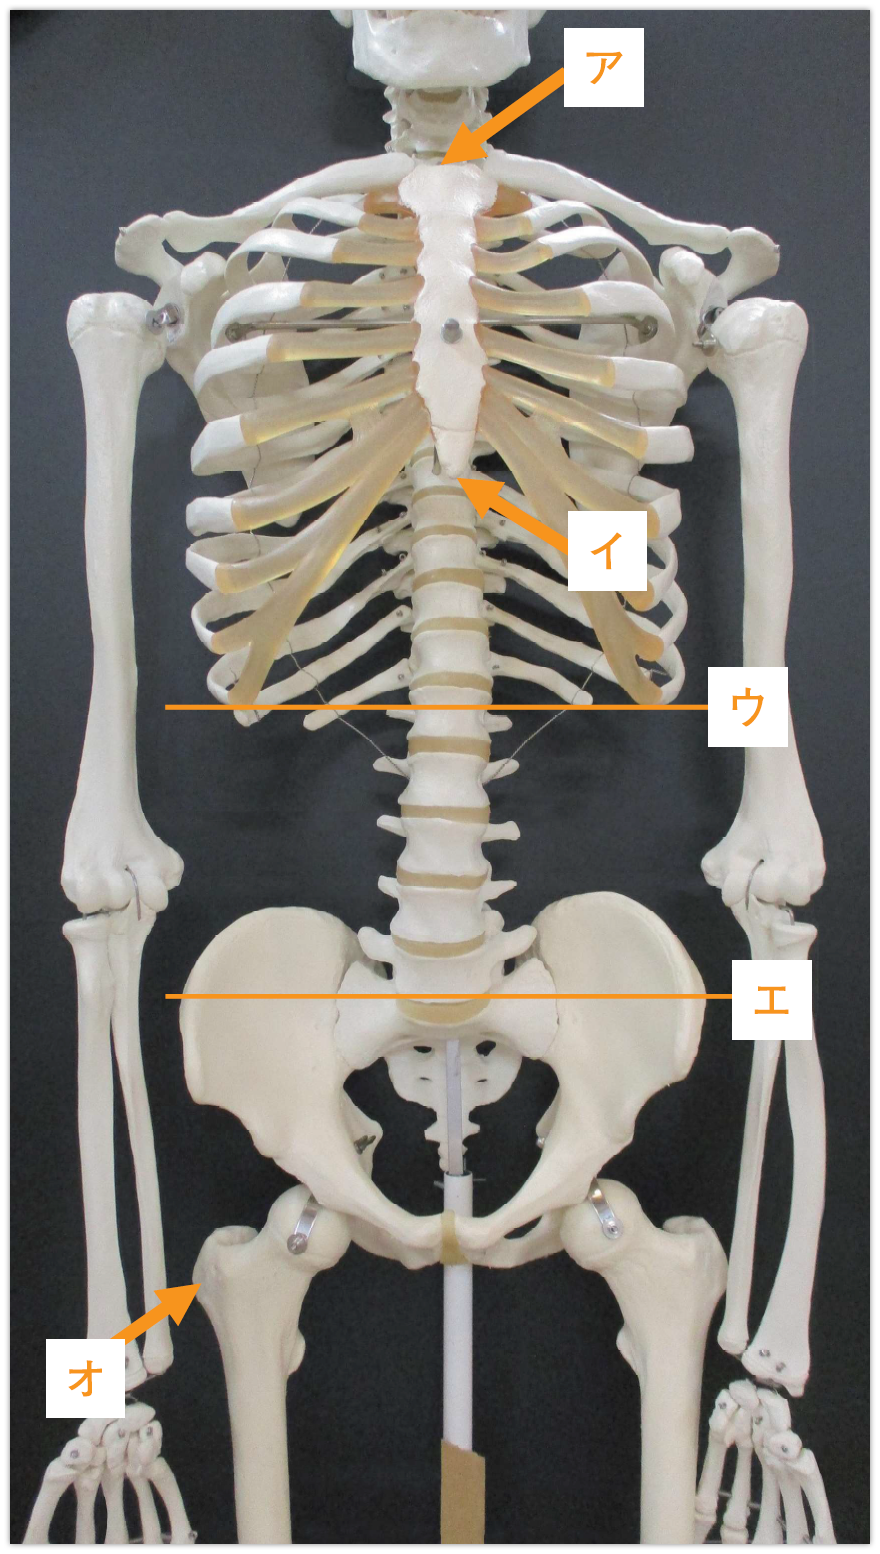

X線撮影における基準点・線(別冊No.7)を別に示す。正しい組合せはどれか。

- 1ア

喉頭隆起

- 2イ

剣状突起

- 3ウ

肩甲骨下線

- 4エ

Jacoby〈ヤコビー〉線

- 5オ

小転子